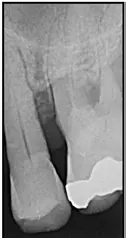

Man benötigt gerade in solchen Situationen ein ausreichendes Sortiment größerer Interdentalraumbürsten, wenn man das Ziel verfolgt, bei der Anwendung den jeweiligen Taschenfundus zuverlässig zu erreichen (Abb. 5).

Sowohl in der initialen Behandlungsphase nach Erstdiagnose einer Parodontitis als auch im Rahmen der Erhaltungstherapie (unterstützende Parodontitistherapie/UPT) besitzt die individuelle Mundhygieneschulung mit regelmäßiger Anpassung von Interdentalraumbürsten eine hohe Relevanz. Die Empfehlung der korrekten und passgenauen Interdentalraumbürste wird allerdings u. a. durch eine zu geringe Auswahl von Produkten mit größerer Reichweite erschwert.